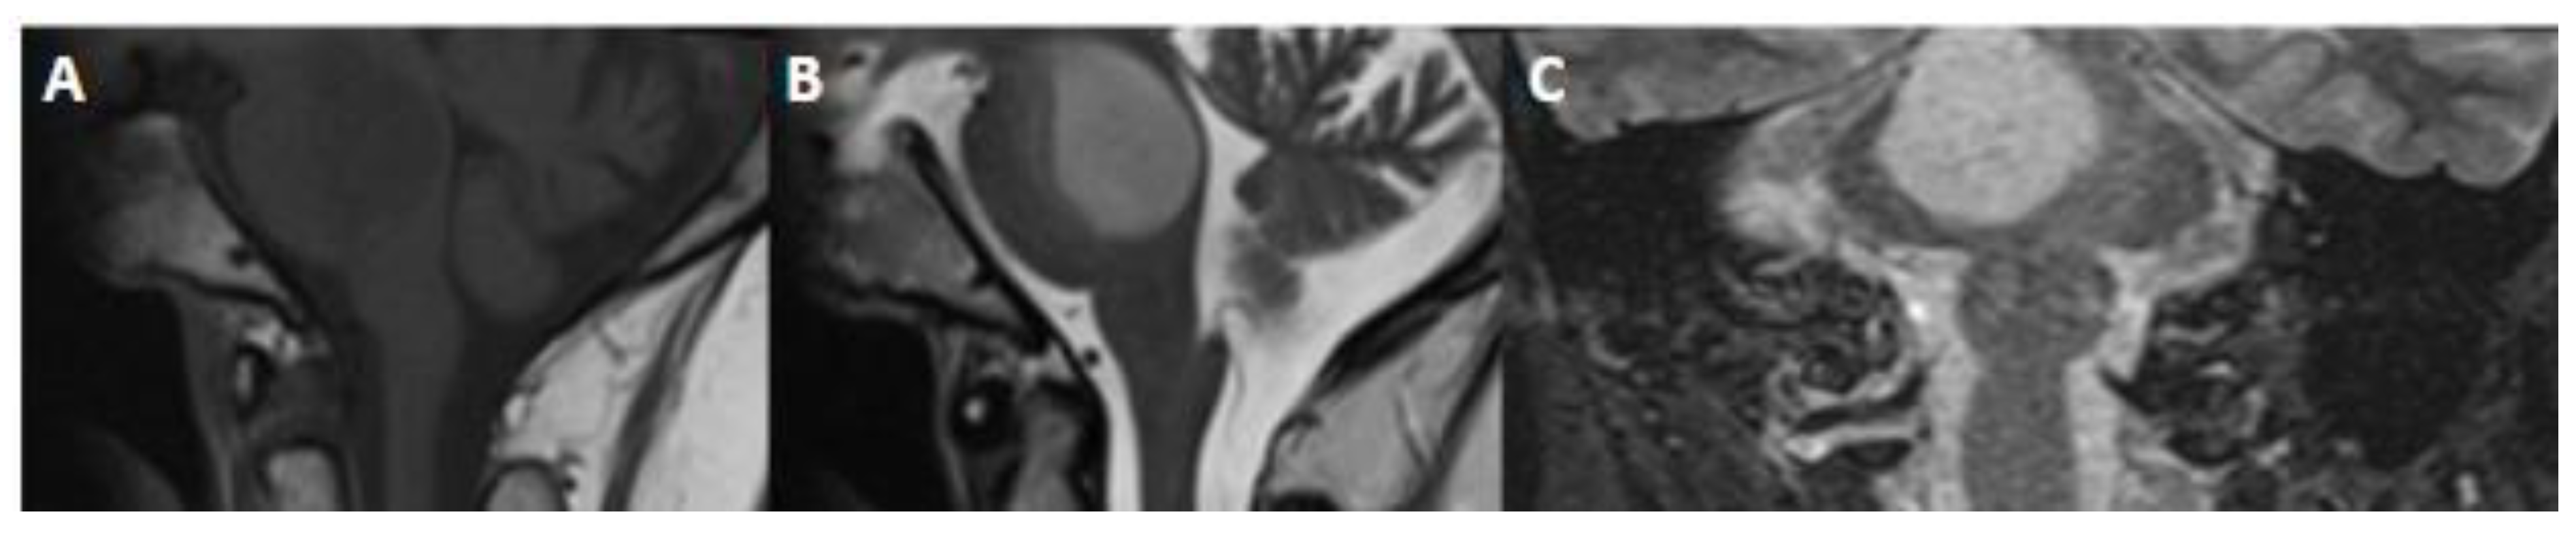

7. Diffuse Midline Glioma, H3 K27-Altered

7.1. Epidemiology and Localization

7.2. Clinical Features

7.3. Brief Genetic Overview

7.4. Imaging

| Diffuse midline glioma, H3 K27-altered | H3 K27, TP53, ACVR, PDGFRA, EGFR, EZHIP | Name changed from H3K27-mutant, | Variable, ill-defined, infiltrative masses, in brainstem, thalamus, or spinal cord, frequently no enhancement, H3.1 subgroup-necrosis and edema likely. |

| Subgroups recognized | |||